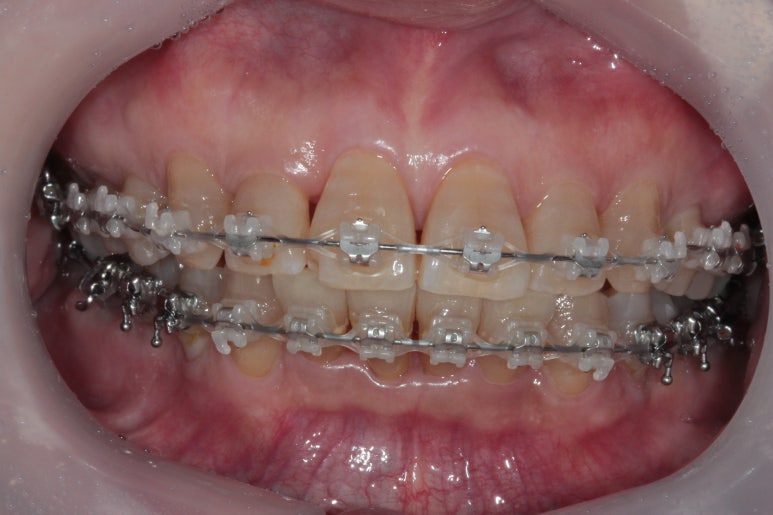

대망의 교정치료 완성의 날.

교정치료가 완성되었습니다!!

비록 앞니가 깨진 것이 조금 눈에 띄긴 하지만... 환자분은 배열만 해도 매우 만족한다 하셔서 이렇게 치료를 마무리 하였습니다. 끝까지 배열이 어려웠던 아래 앞니의 가지런함이 눈에 띕니다.

교합평면도 평평하게 조화롭게 완성된 것을 보실 수 있습니다.

생각보다 평평한 교합평면을 달성해내는 것은 어려운 과정입니다.

씹는면에서 보아도 상당히 가지런히 완성된 것을 보실 수 있습니다.